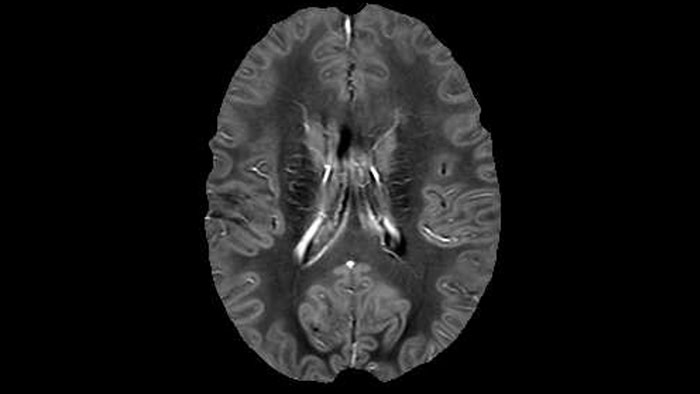

“In addition to traditional imaging like FLAIR for lesion identification, we see a real push towards techniques that weren’t normally required for MS, including good highresolution 3D T1 weighted images to do volumetrics. We’ve also started looking at spinal cord imaging again, since techniques have improved in terms of acquisition and analysis. Another important technique is susceptibility weighted imaging (SWI), particularly if we are looking for central veins in lesions, which is extremely helpful for diagnosis.”

He says the accelerated scanning is achieved via the use of Compressed SENSE and MultiBand SENSE. “We can use Compressed SENSE acceleration factors of about 10 on a 3D FLAIR for instance, which is quite remarkable compared with what we saw with the Achieva. With 3D FLAIR, we can push the spatial resolution to 0.3 cubic mm and it works. Previously, our 3D FLAIR scans lasted about 8 minutes, but now with Elition they are five minutes. The SNR is also visibly better. Our SWI and QSM scans look fantastic. Also, since a lot of neuroimaging is EPI based, using the MultiBand SENSE technique can increase temporal resolution and make it possible to run complicated DTI scans relatively quickly.”

QSM based on a Compressed SENSE multi-echo SWI.